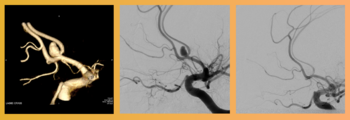

La neuro-réanimation à l'hôpital de la Citadelle